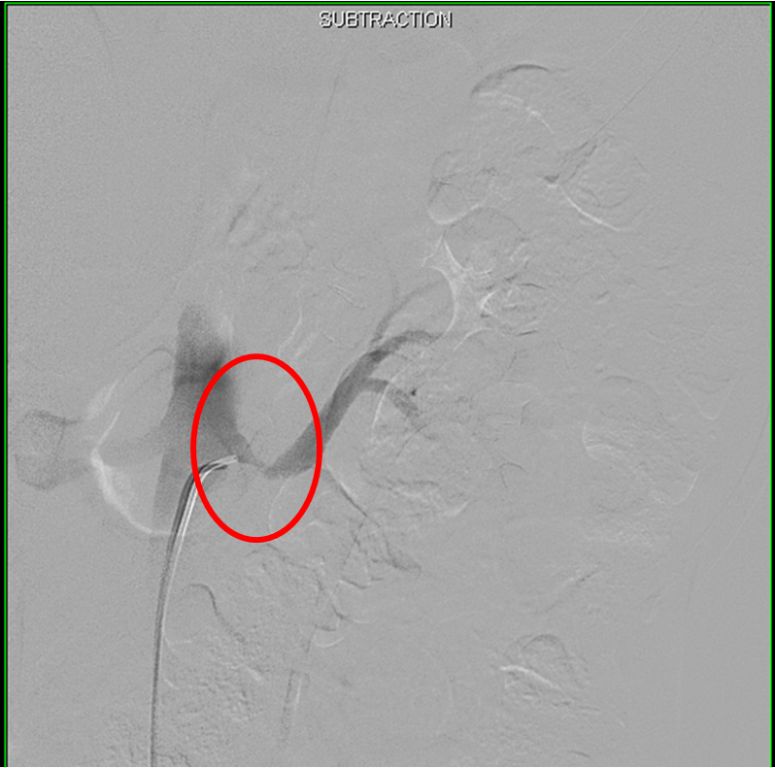

When intervention is required, treatment of cerebral FMD is usually done with catheter directed angioplasty. It is offered for symptomatic patients. There is actually not much data comparing catheter directed treatment with surgery.

- Angiography – Angiography is the “gold standard” for detection of fibromuscular dysplasia. It can detect lesions as small as 200-300 micrometers. Angiography has the advantage of assessing lesions with IVUS and pressure measurements. Only these internal measurements can truly assess disease severity. However, they are only rarely needed from a clinical standpoint.